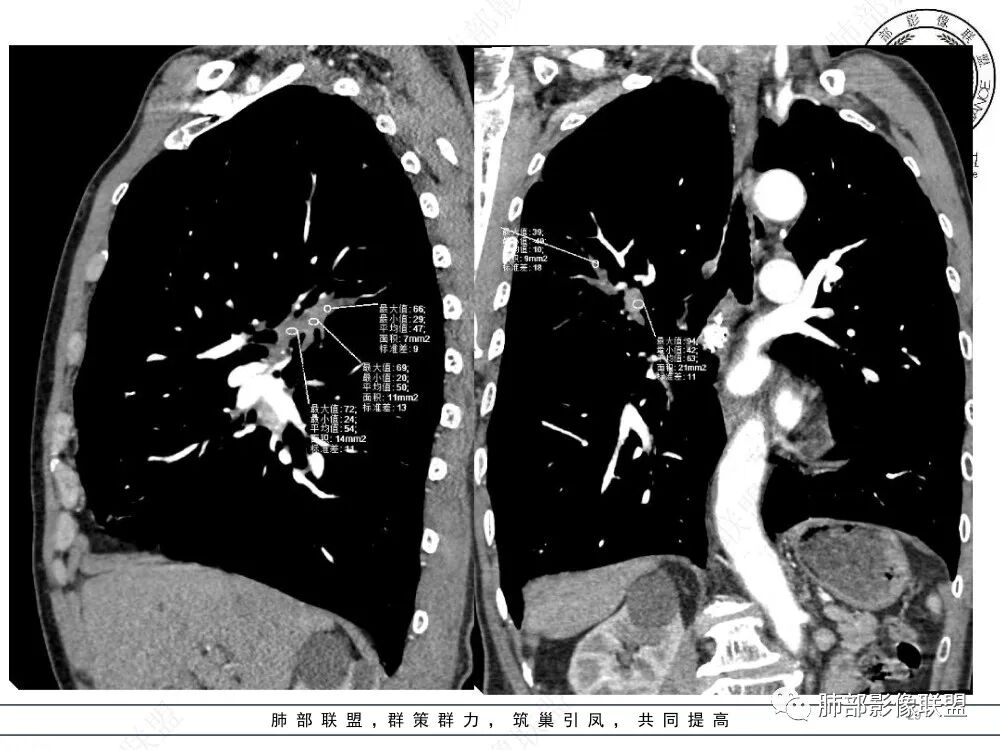

3、影像表现:肺气肿背景,右肺上叶后段支气管开口阻塞并见腔内软组织影轻度突向叶支气管,阻塞段以远支气管及分支扩张填塞呈指套样改变,轻度不均匀强化,外周点片影,符合阻塞性炎性表现,现有图像资料未见明确肺门纵膈淋巴结增大。

上图,鳞癌,腔内软组织占位,局部膨大,不均匀强化,伴远端粘液栓。